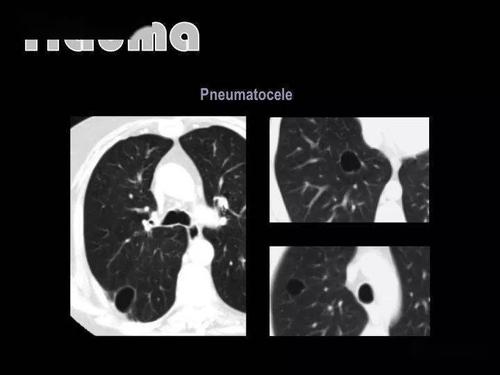

肺大泡,肺气肿,肺气囊,囊肿,空洞,ct如何鉴别?

如何区分"肺大疱","肺气囊","肺囊肿"

你报错了多少"肺气囊"?

肺气肿,肺大泡,肺气囊有什么不一样?